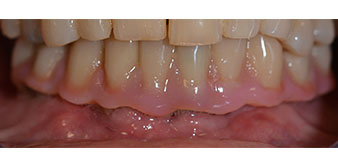

Пациентката е 64-годишна жена с частично обеззъбяване на зъби 38, 33 и 43 и частична долночелюстна протеза (Фиг. 1 и 2).

частично обеззъбяване

Фиг. 1

Фиг. 2